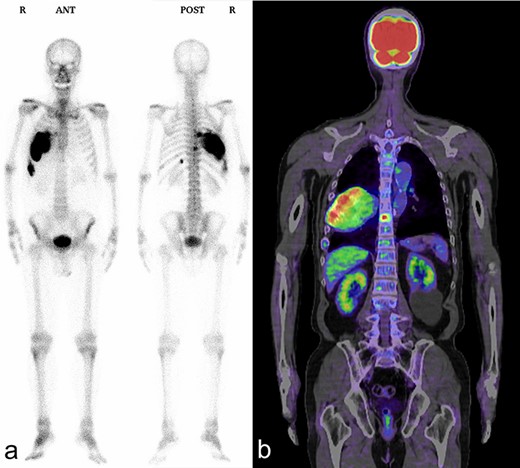

A 72-year-old man was referred to our department with a suspected tumor in the right rib. An abnormal shadow in the right chest was found during screening at 50 years of age. The patient was later followed up intermittently by a general physician (Fig. 1a and b). At 72 years of age, he was referred to our department because of a suspected malignant tumor. There were neither subjective symptoms nor abnormal physical findings. A blood test revealed an elevated level for alkaline phosphatase alone at 706 U/L. A pulmonary function test showed a percent vital capacity (%VC) of 78.8%, indicating a mild restrictive impairment. Plain radiography showed a radiopaque tumor measuring 12 × 9 × 18 cm that was connected to the seventh rib in the right thoracic cavity (Fig. 1c). When compared to previous images, the tumor had gradually grown over the preceding 22 years. Computed tomography (CT) showed an extra-osseous tumor-like lesion with calcification, cortical destruction of the right seventh rib and a similar small lesion in the right ninth rib (Fig. 2). Moreover, lesions were also detected in the ninth thoracic vertebral body. Magnetic resonance imaging (MRI) revealed a lower signal intensity inside the lesion compared to the muscle on T1-weighted images and a mixture of low and high intensity on T2-weighted images, while enhancement was observed in the lower intensity area on T2-weighted images (Fig. 3a and b). Bone scintigraphy and positron emission tomography/computed tomography (PET/CT) revealed an increased uptake in the right seventh and ninth ribs and ninth vertebral body, and the right seventh rib showed a high standard uptake value at 7.67 on PET/CT (Fig. 4a and b).

Bone scintigraphy and PET/CT shows an increased uptake in the right seventh and ninth ribs and ninth thoracic vertebral body. (a) Bone scintigraphy; (b) PET/CT.

An enlarged lesion of fibrous dysplasia after bone maturation may suggest malignant transformation. Fibrous dysplasia undergoing malignant transformation often presents with hyper alkaline phosphatemia, and plain radiography or CT often reveal osteolysis or disruption of the cortex [3]. Fluorodeoxyglucose-positron emission tomography/computed tomography (FDG-PET/CT) is reportedly useful for differentiating fibrous dysplasia from metastatic bone tumors and for its early diagnosis of malignant transformation [4]. Our patient presented with hyper alkaline phosphatemia, and CT revealed an extra-osseous mass with cortical bone destruction and calcification. FDG-PET/CT showed strong abnormal accumulation. Furthermore, malignant transformation to low-grade sarcoma was suspected due to the continued growth of the lesion. However, diagnostic imaging for malignant transformation has been reported to cause false-positive results [5, 6]. Therefore, we performed multiple preoperative CT-guided needle biopsies and incision biopsies from multiple sites to confirm that there were no malignant pathological findings before surgery. No malignant findings were found in the final pathological diagnosis of the resected specimen.